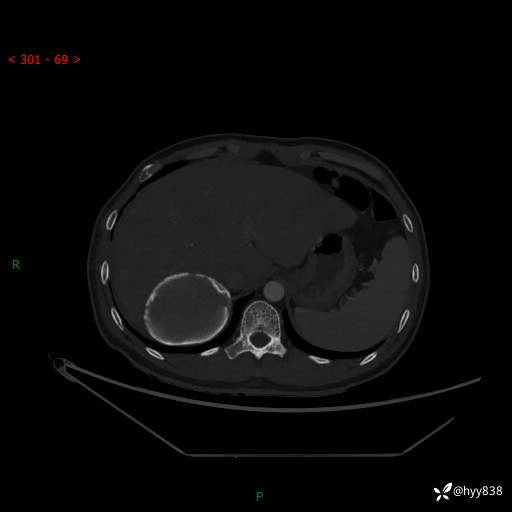

性别:男

年龄:50岁

简要病史:夜尿增多半月,发现肾功能异常1天,超声发现腹膜后占位

腹部CT平扫+增强

增强